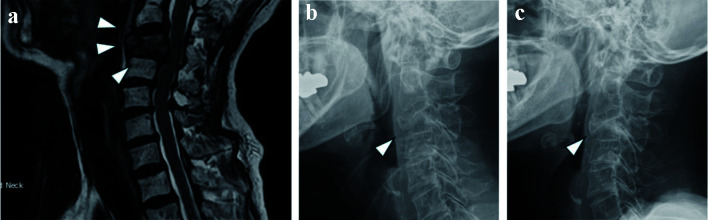

骨是乳腺癌转移的常见部位,脊柱表现出特别高的亲和力。一位83岁的日本老年痴呆症患者在左乳房出现可触及的肿块。穿刺活检显示浸润性乳腺导管癌,激素受体阳性,人表皮生长因子受体2 (HER2)阴性,伴有淋巴结转移。胸部动态计算机断层扫描未见远处转移。她被诊断为光型,IIB期(T2N1M0)乳腺癌,并接受了手术。在全麻诱导过程中,由于气道水肿插管困难,需要支气管镜检查。手术后第二天,她报告颈部疼痛,x线摄影显示第三颈椎压缩性骨折。磁共振成像证实在第三颈椎有转移性病变。术后,患者接受来曲唑内分泌治疗,唑来膦酸放射治疗,宫颈转移患者接受颈套。7个月后,骨溶解病变钙化,疼痛减轻。这个病例是独特的,因为乳腺癌的单独颈椎转移,导致压缩性骨折和气道水肿,是罕见的。该病例强调了在出现气道困难或不明原因颈部疼痛的乳腺癌患者中考虑宫颈转移的重要性,特别是在围手术期。早期识别和干预对于预防并发症和优化患者预后至关重要。

Bone is a common site of breast cancer metastasis, with the spine showing a particularly high affinity. An 83-year-old Japanese woman with Alzheimer's disease presented with a palpable mass in her left breast. A needle biopsy revealed invasive ductal carcinoma of the breast, hormone receptor-positive, human epidermal growth factor receptor 2 (HER2)-negative, with lymph node metastasis. Chest dynamic computed tomography showed no distant metastases. She was diagnosed with luminal-type, stage IIB (T2N1M0) breast cancer and underwent surgery. During induction of general anesthesia, intubation was difficult due to airway edema, necessitating bronchoscopy. The day after surgery, she reported neck pain, and radiography revealed a compression fracture of the third cervical vertebra. Magnetic resonance imaging confirmed a metastatic lesion in the third cervical vertebra. Postoperatively, she received endocrine therapy with letrozole, radiation therapy with zoledronic acid, and a cervical collar for cervical metastases. Seven months later, the osteolytic lesion calcified, and her pain improved. This case is unique because solitary cervical vertebral metastases from breast cancer, leading to compression fractures and airway edema, are rare. The case highlights the importance of considering cervical metastases in patients with breast cancer who develop airway difficulties or unexplained neck pain, particularly in the perioperative setting. Early recognition and intervention are crucial for preventing complications and optimizing patient outcomes.